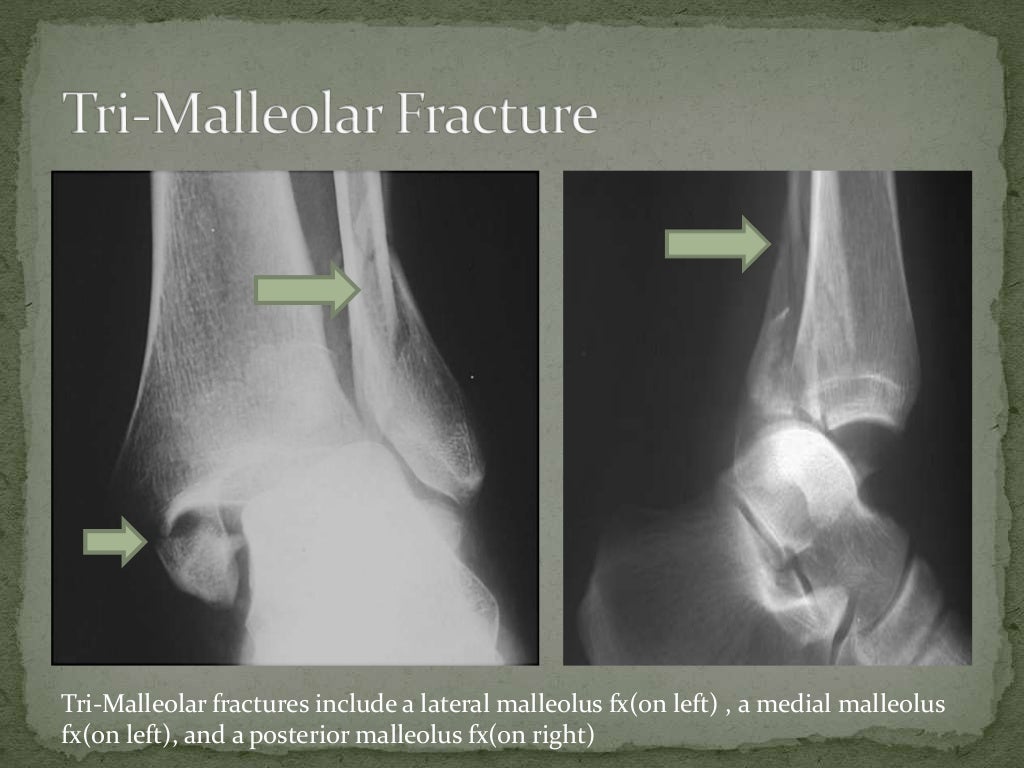

4,5,6 The relationship between ankle fractures and osteoporosis is less clear while some studies identified ankle fractures as osteoporotic, others failed to identify any significant relationship between bone mineral density measurements and such injuries. There are several risk factors for ankle fractures, including obesity, multiple falls, and alcohol consumption. 3 Men are more likely to sustain ankle fractures at younger ages than are women. 1,2 High-energy trauma can also result in ankle fractures, commonly with suprasyndesmotic patterns. Elderly women are especially susceptible to these injuries, reporting the highest incidence of ankle fractures, particularly bimalleolar and trimalleolar patterns. Low-energy trauma accounts for the majority of ankle fractures. Because the joints in the lower limb act in concert during the gait cycle, any deviation from the normal function of one joint can have significant implications on the function of the other joints. Disregarding the precise details of these fractures can lead to disappointing outcomes. Case Overview BackgroundĪnkle fractures are among the most commonly encountered fractures in orthopedics nevertheless, their frequency should not undermine their seriousness. Weaver discusses the surgical landmarks and approaches to the ankle, the methods of fixing the malleoli and the syndesmosis, and common concerns that arise during the surgical management of ankle fractures.

Weaver walks us through the surgical management of a 23-year-old male who sustained a trimalleolar ankle fracture with concomitant dislocation and syndesmotic injury following a motor vehicle collision. Operative management is recommended for most displaced fractures, fractures with dislocations, and open fractures. 1, 2 The goal of management is to restore a stable and congruent joint. Ankle fractures are the second most common lower limb fractures after those involving the hip, accounting for 10% of all fractures, with an incidence that has been increasing.